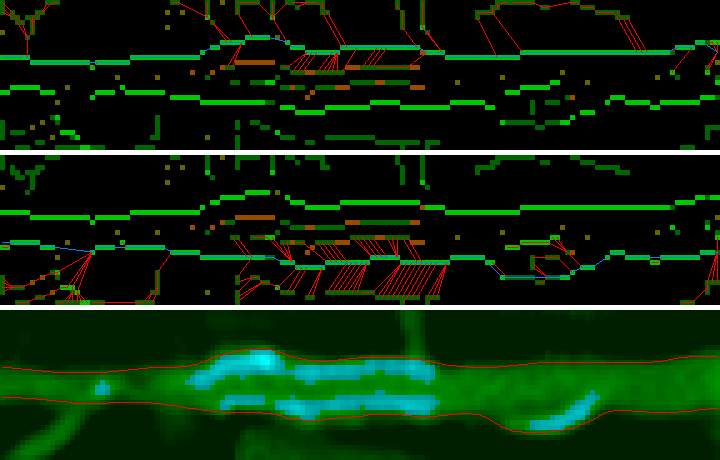

Нашу стопку срезов, полученную на предыдущем этапе, мы режем восемью плоскостями (по аналогии с разрезанием торта) и все вычисления проводим уже в пространстве плоскостей:

Если отобразить нормализованные значения интенсивностей вокселей, попавших на режущую плоскость, то получим такую картину:

Для обнаружения границ сосуда используется классический подход (edge detection by gradient) совместно с поиском пути. Схема:

5. Все оставшиеся воксели считаются границами. На основании значения градиента, порога кальция (который доступен не сразу) и близости к “вертикальному” центру, каждой точке присваивается определенная стоимость (чем ярче воксель, тем выше его приоритет при поиске пути):

В таком виде границы сосуда уже практически однозначно определены.

6, 7. Чтобы построить границы воспользуемся поиском пути. В качестве начальной и конечной берутся ближайшие крайние точки с наименьшей стоимостью. Для поиска пути используется обычный поиск в ширину, который выбирает граничные точки с наименьшей стоимостью. Также доступны прыжки, но цена их высока. Верхняя и нижняя границы сосуда ищутся раздельно, и после к ним применяется сглаживание:

Такая процедура выполняется для каждой плоскости, что в результате дает шестнадцатисегментные кольца для каждого среза в стопке. Эти кольца формируют внешние границы сосуда.

Как видно из изображения, есть участки, в которых границы обнаружены неправильно. Это происходит из-за наличия кальция, что в результате приводит к обнаружению границ кальция, а не границ сосуда. Чтобы такого не происходило после первого обнаружения границ необходимо определить порог кальция (об этом дальше), а затем выполнить второе обнаружение границ, игнорируя воксели, относящиеся к кальцию. Тогда получим: